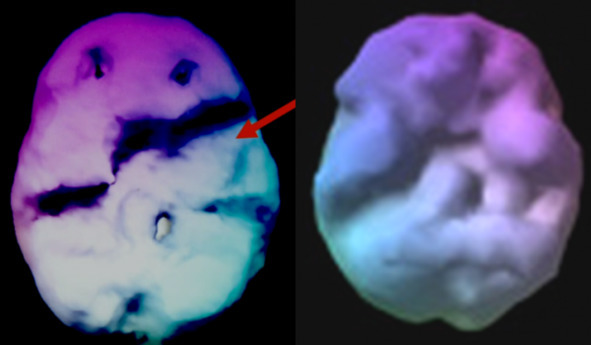

Но Эндрю повезло с дядей. В своей клинике доктор Амен использует технологию SPECT Imaging для сканирование активности мозга. После скана мозга Эндрю выяснилось, что на месте левой височной доли мозга у мальчика была киста размером… с мячик для гольфа.

На картинке слева – мозг Эндрю. Обратите внимание на пробои в активности.

На картинке справа – здоровый мозг. Активность распространена равномерно.